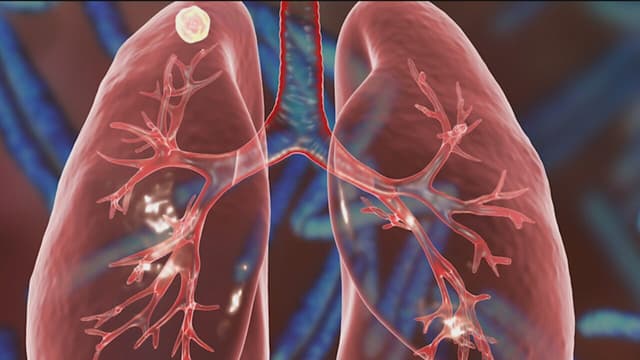

Chỉ số tầm soát ung thư phổi thông qua xét nghiệm máu là các chất chỉ điểm quan trọng giúp xác định các dấu hiệu bất thường của ung thư phổi trong giai đoạn tiền ung thư. Tuy nhiên, khi chỉ số tầm soát ung thư phổi cao bất thường, thì người bệnh nên làm […]

Nhiều người thường chủ quan và bỏ qua những triệu chứng nhẹ, thông thường như: ho, khàn tiếng, mệt mỏi,…Tuy nhiên, ít ai biết rằng đó là “cảnh báo” ngầm cho sự xuất hiện của ung thư phổi giai đoạn đầu. Nếu không kiểm tra tầm soát ung thư phổi thì rất dễ tạo cơ […]